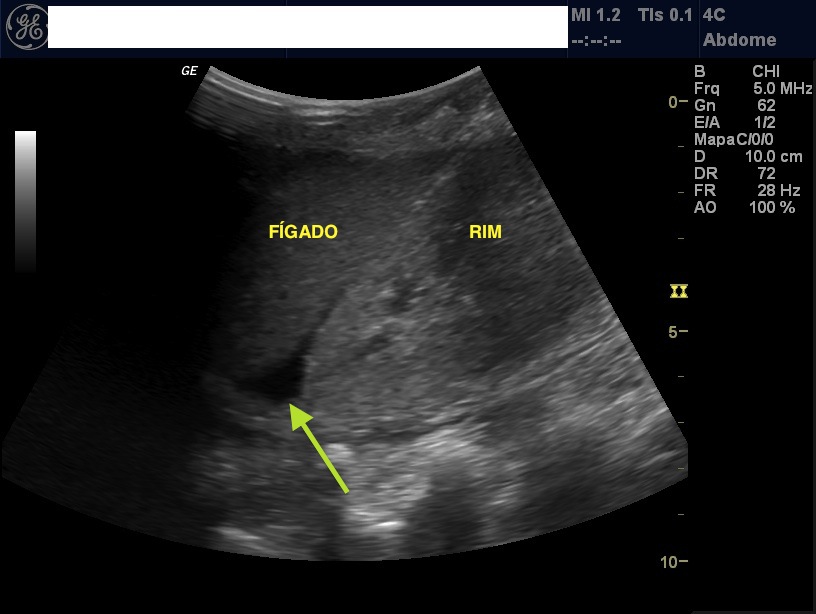

Considerando as características ecográficas do parênquima hepático, o diagnóstico da EH é baseado no aumento gradativo da ecogenicidade e da atenuação do feixe sonoro, sendo que, quando presentes, as alterações texturais são discretas e de menor relevância.

As alterações do fígado observadas pela ecografia foram: ecos finos do parênquima hepático com visualização normal do diafragma e de vasos intra-hepáticos; aumento difuso nos ecos finos com visualização prejudicada dos vasos intra-hepáticos e diafragma; e aumento importante dos ecos finos com visualização prejudicada ou ausente dos.

O fígado esteatósico apresenta-se ecograficamente com aumento da ecogenicidade do parênquima atenuando a penetração do feixe ultrassónico. Na tomografia computorizada sem contraste, o fígado esteatósico apresenta valores de densidade inferiores a 40 UH.

O que é Ecogenicidade aumentada no fígado? Aumento difuso e homogêneo da ecogenicidade hepática,encontrado em doenças de depósito (das quais a esteatose é a mais frequente-grau severo). Caro, os dois achados ecográficos são compatíveis com o acúmulo de gordura no fígado, ou seja esteatose hepática. O que significa.